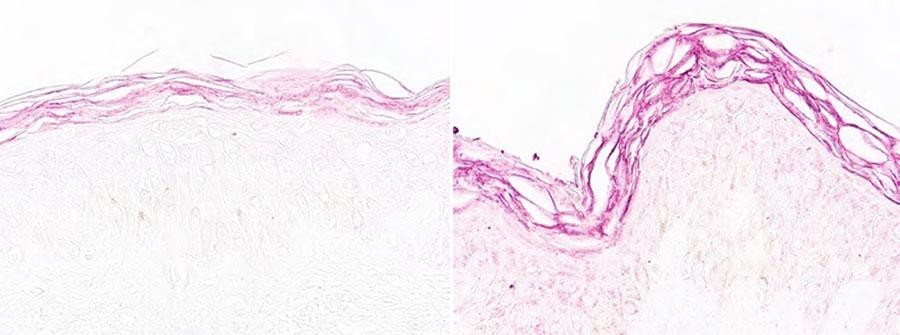

为了尽可能模拟现实使用环境,测量面霜配方对肌肤的作用,娇兰进行了一项离体测试(皮肤外植体),成功证明主要成分的焕活能力,初次使用即可见效,令肌肤绽现年轻态。

坚持使用 肌表透现 焕活新生

I型胶原蛋白

使用前(左图);使用后+60%(右图)

纤维蛋白 (弹性纤维)

使用前(左图);使用后+70%(右图)

神经酰胺

使用前(左图);使用后+58%(右图)